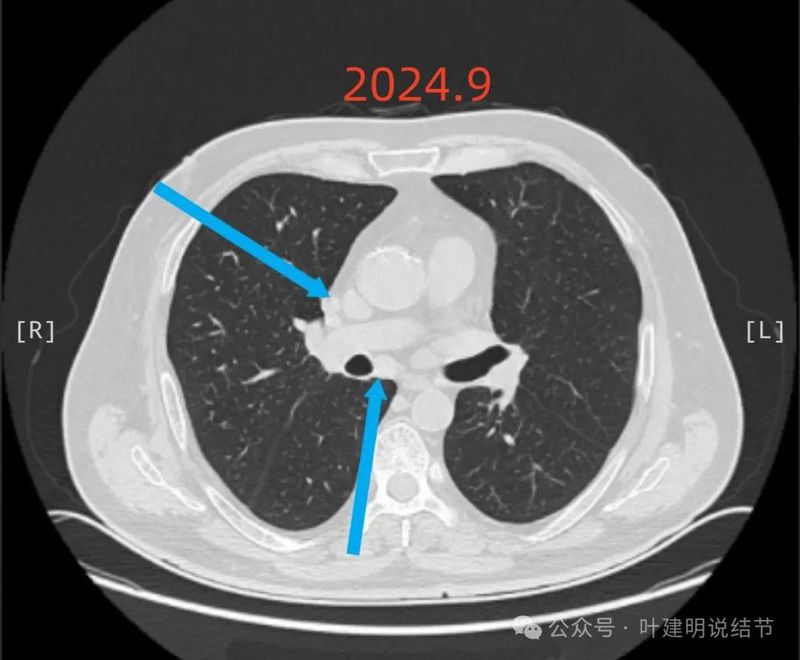

2024年9月24日 病人感冒,咳嗽,入住当地三甲医院,依然按炎症处理,此时左肺上叶段结节14*9mm,右肺上叶5*4mm结节, 引起重视,CT及影像见附件1 ;

2024年9月再增大进展,见血管进入明显,靠血管这侧的边缘较为毛糙。

上图是2024年9月的,隆突下也有肿大淋巴结。